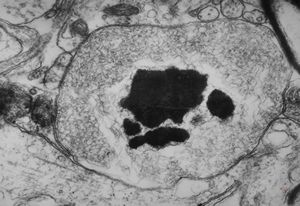

M,10y. | herpetic encephalitis